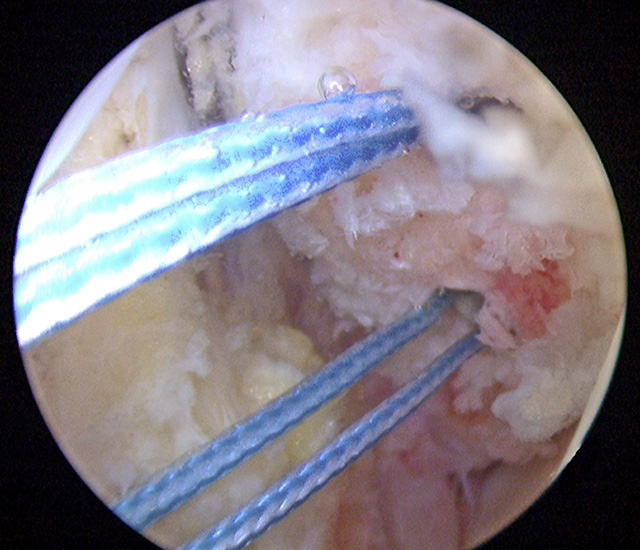

Operationstechnik

Nachfolgend wird die OP-Technik an einem rechten Sprunggelenk unter Verwendung von PEEK-Ankern veranschaulicht.

Video 1

Intra- und extraartikuläre Darstellung des Operationsablaufs am linken Sprunggelenk mit selbstschneidenden Titanfadenankern.